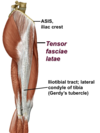

Tensor Fascia Lata

- ASIS, iliac crest–> IT tract, gerdys tubercle

- Superior gluteal n L4-S1

- actions

- abduction of the hip